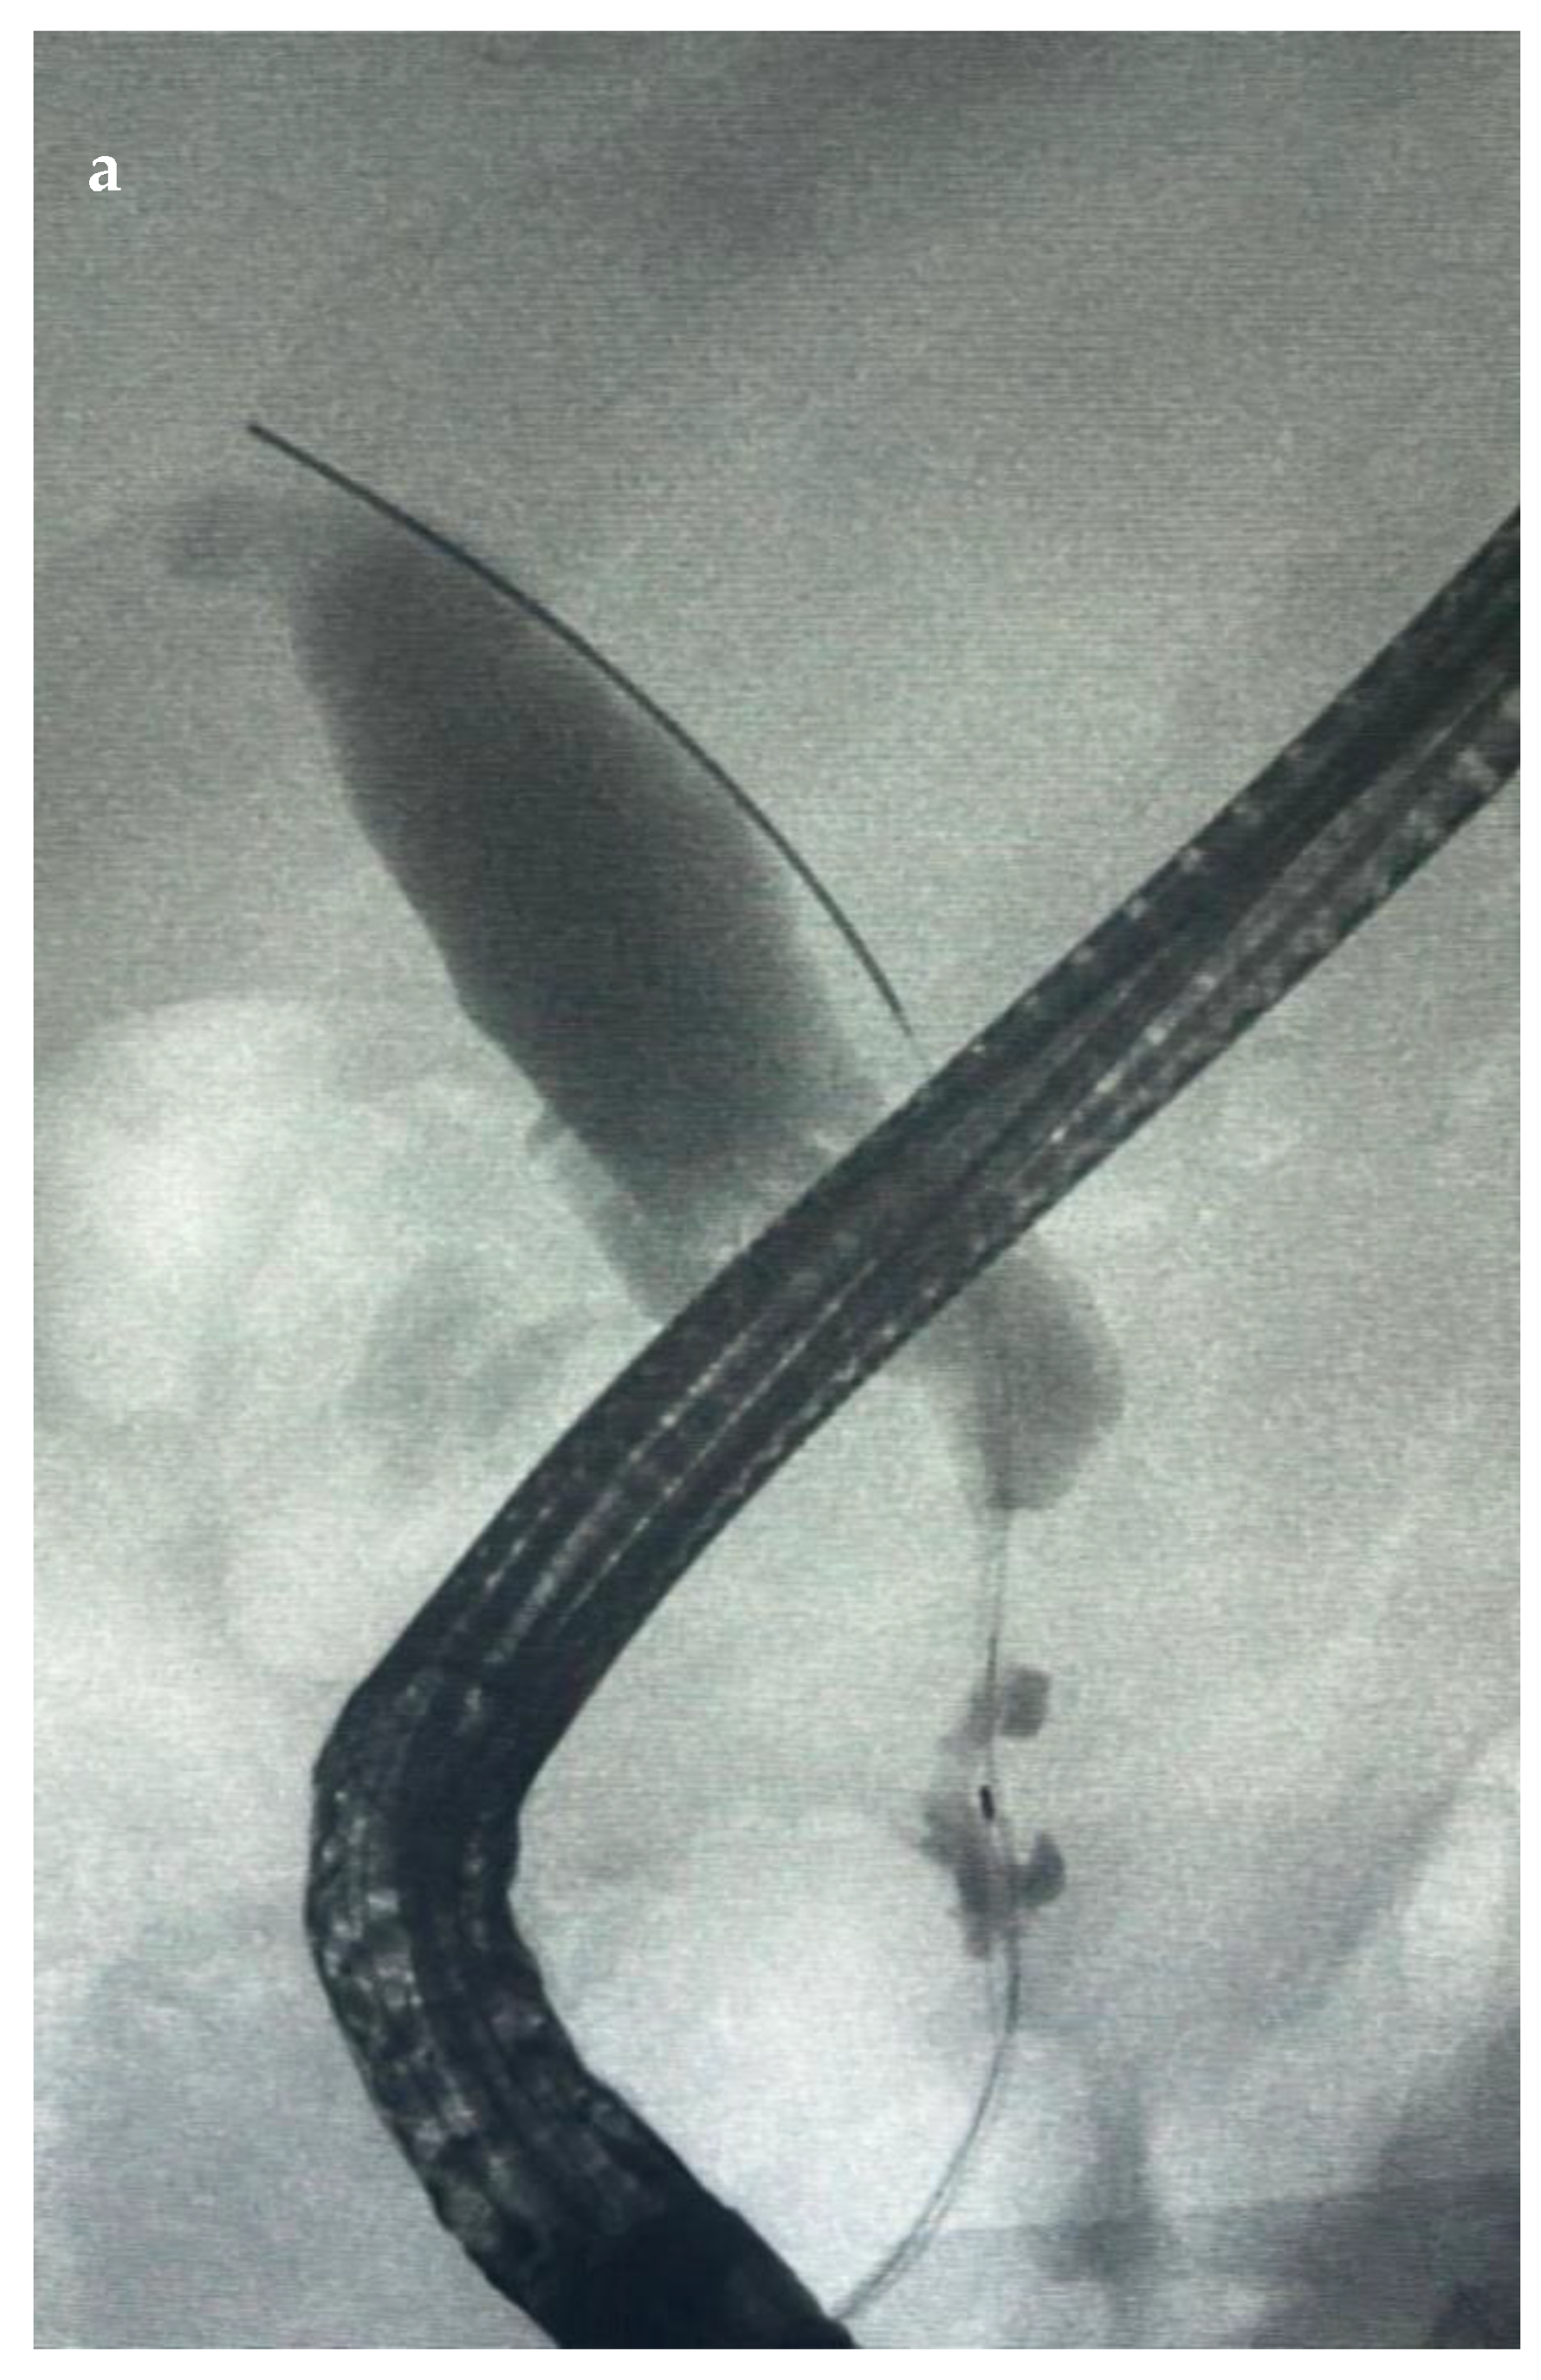

6.4.2. Endoscopic Retrograde Cholangiopancreatography (ERCP)

7.1.2. Endoscopic Nasobiliary Drainage (ENDB)

7.1.3. EUS-Guided Biliary Drainage (EUS-BD)